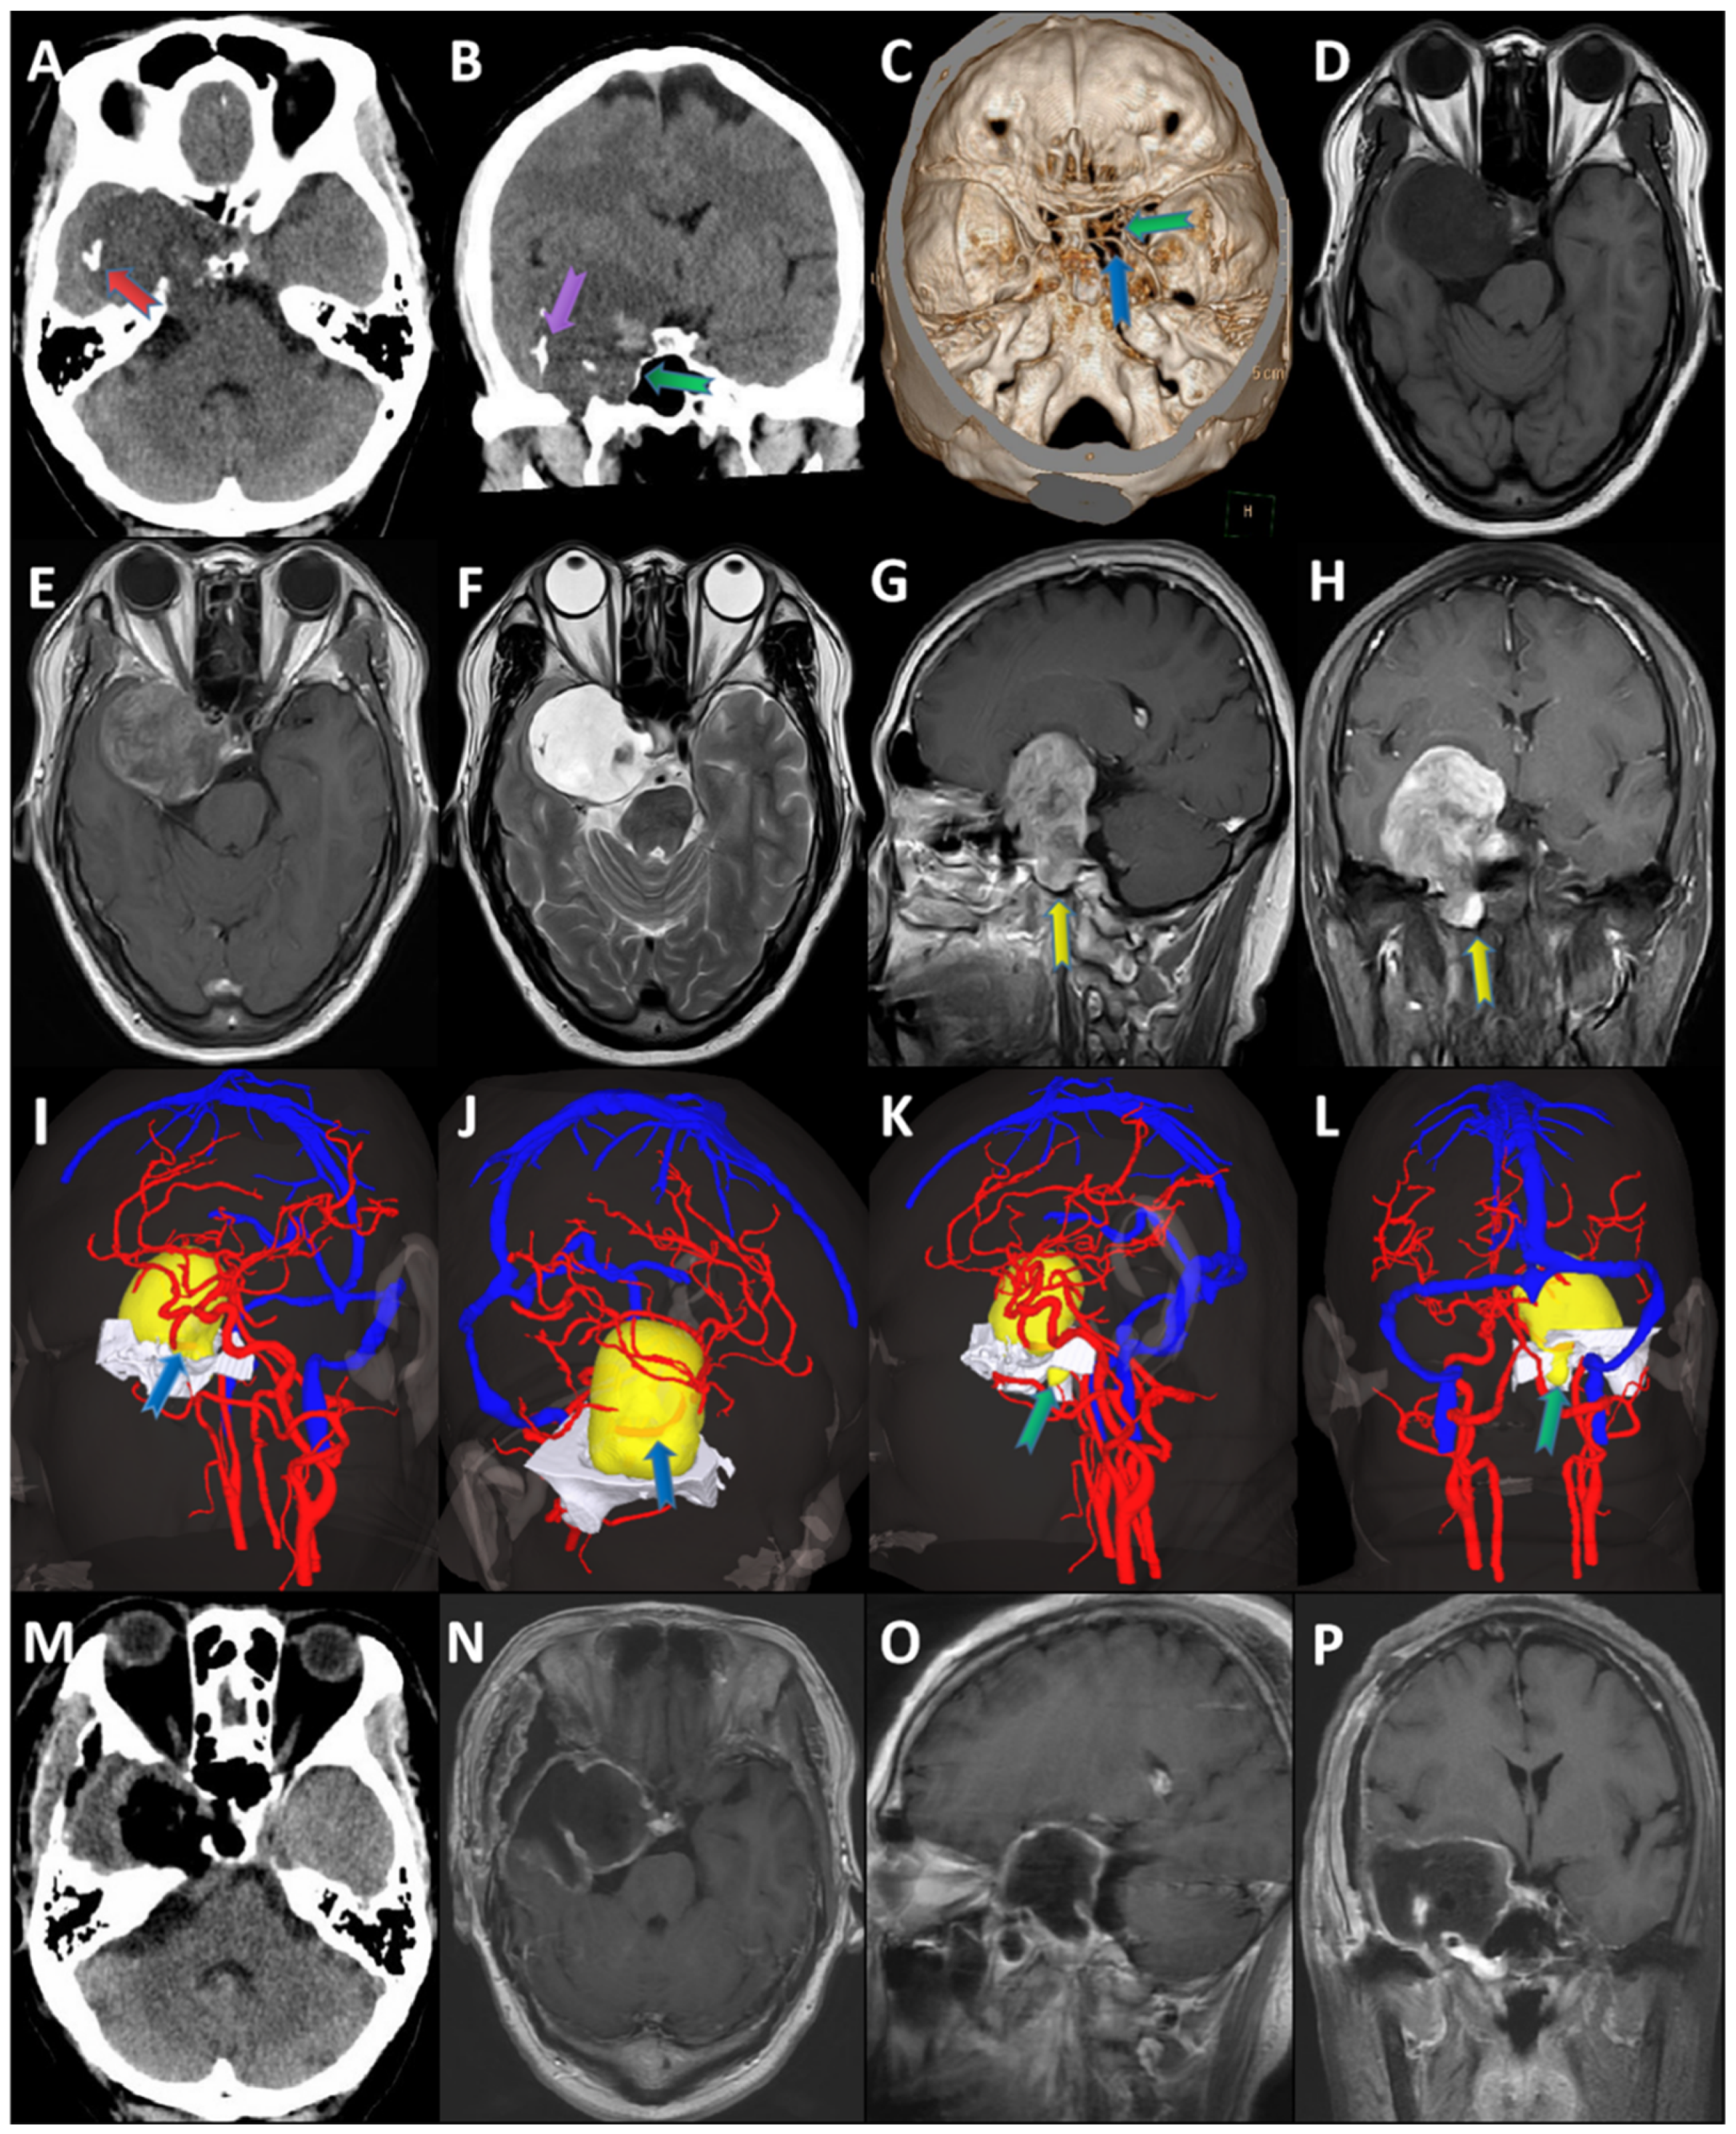

3.2. Radiological Profiles

3.3. Surgical Resection

3.4. Histopathology